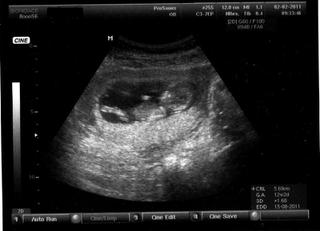

:-D dobre ... tu je Jonatan teraz, 11+4tt, ale velkostou 12+5tt :-D To svetle zospodu je placenta, lezi si na nej ako na vankusi x-)

@charlize leží na chrbátiku s rukou na brušku? aký kráľ :-)

no tak to je vážny pán!!!! jeden vegetak. inac nadherny tvar hlavy ma. jeden cukrik :) dievcata budu spokojne :)